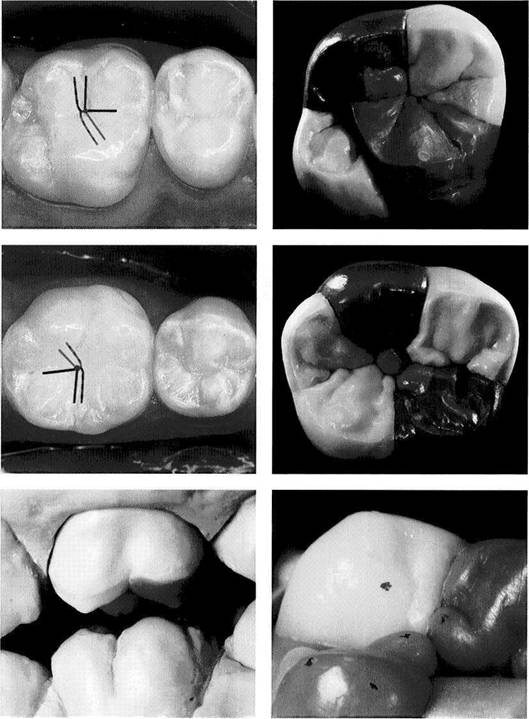

Occlusal Analysis Using Sectioned Casts

With the help of a sectioned mandibular cast with remov­able teeth mounted in centric it is possible to repeatedly experiment with alterations of the occlusion through selec­tive reduction of the teeth. With this method one can calcu­late, before cutting away any of the occlusal surfaces of the stone casts, approximately how much tooth structure would have to be removed to achieve the desired equilibration. A step-by-step analysis can be made on the mounted casts to determine how the planned corrections would affect the cuspal relationships and the vertical dimension. At this stage, then, it is possible to foresee whether the occlusion

can be stabilized through selective grinding alone or if prosthodontic or orthodontic measures will also be neces­sary. In some cases we also use occlusal analysis on sec­tioned casts as a tool for explaining the proposed treatment to the patient. The reasons for the planned occlusal reshap­ing of the natural teeth and the changes that can be expected must be thoroughly discussed with the patient.

Materials for occlusal

analysis with the help of a

segmented cast

Maxillary and mandibular casts are mounted in a relationship to the articulator corresponding to that of the natural teeth to the cranium and joints. The segmented mandibular cast with removable teeth has also been mounted in centric and thus is interchangeable with the solid mandibular cast. Strips of shim stock cut to the width of a premolar are used to test the occlusal con­tacts.

All of the posterior teeth and at least the lower canines should be removable as individual segments.

Centric occlusion

The segmented mandibular cast has been substituted for the solid mandibular cast.

The upper member of the articula­tor is closed to the first occlusal contact.

Preliminary inspection suggests that occlusal equilibration by selec­tive grinding could be accom­plished only with considerable loss of tooth structure in the molar region.

651 Lingual view of the teeth in centric occlusion

In this lingual view the functional open bite in the premolar and ante­rior region becomes especially ap­parent.

652 Shim stock test and removal of the interfering segments

The pair of teeth making premature contact is located with the help of shim stock, and the corresponding tooth is removed from the mand­ibular cast.

Left: Before the first tooth segment is removed, the setting of the in-cisal pin with the assumed prema­ture centric contact is read from the millimeter scale (here -1 mm). This number is recorded for further evaluation.

653 Further shim stock tests

Following elimination of the poste­rior occlusion in this example, the sole remaining tooth contact is found in the right canine region.

Left: The incisal pin setting after re­moval of all posterior tooth seg­ments (here+1 mm).

654 Occlusal discrepancy in the anterior region

The only remaining centric prema­ture contact now lies on the lingual guiding surface of the maxillary right canine. The anterior horizon­tal overlap is still too great to allow an initial incisal guidance.

Left: Corresponding situation on the opposite side.

655 Occlusal relationship after removal of both mandibular canines